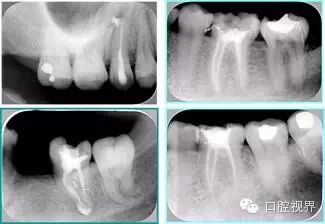

共有 4 张 X 线片,分别是术前、诊断丝 、主牙胶尖确认、术后。

( 1 )术前:术前 X 线片用来了解牙齿的大概情况。术前预期为多根牙时 X 线片应偏头拍摄。

( 2 )诊断丝:根据术前 X 线片进行开髓、根管的初步预备后,需要插入诊断丝,用来指示工作器械位置。常用 10 号或 15 号扩大器作为诊断丝插入牙髓腔。

( 3 )主牙胶尖确认:通过术前预期和诊断丝诊断,明确工作长度、牙根走向,进行根管预备。之后应进行主牙胶尖(中锉)确认,已明确根管是否适合充填。

( 4 )术后:观察治疗效果。